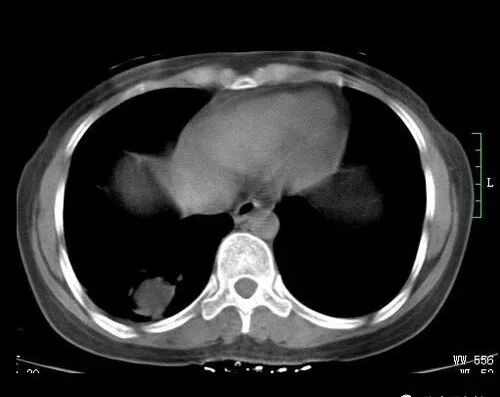

现代人生活节奏快,工作压力大,精神高度紧张,如果不注意饮食作息以及保持良好心态,往往容易使机体代谢紊乱,导致痰和淤血堆积在体内。例如在颈部可见甲状腺结节,在胸部可见乳腺增生、乳腺结节,在女性盆腔可见子宫肌瘤卵巢囊肿等等。